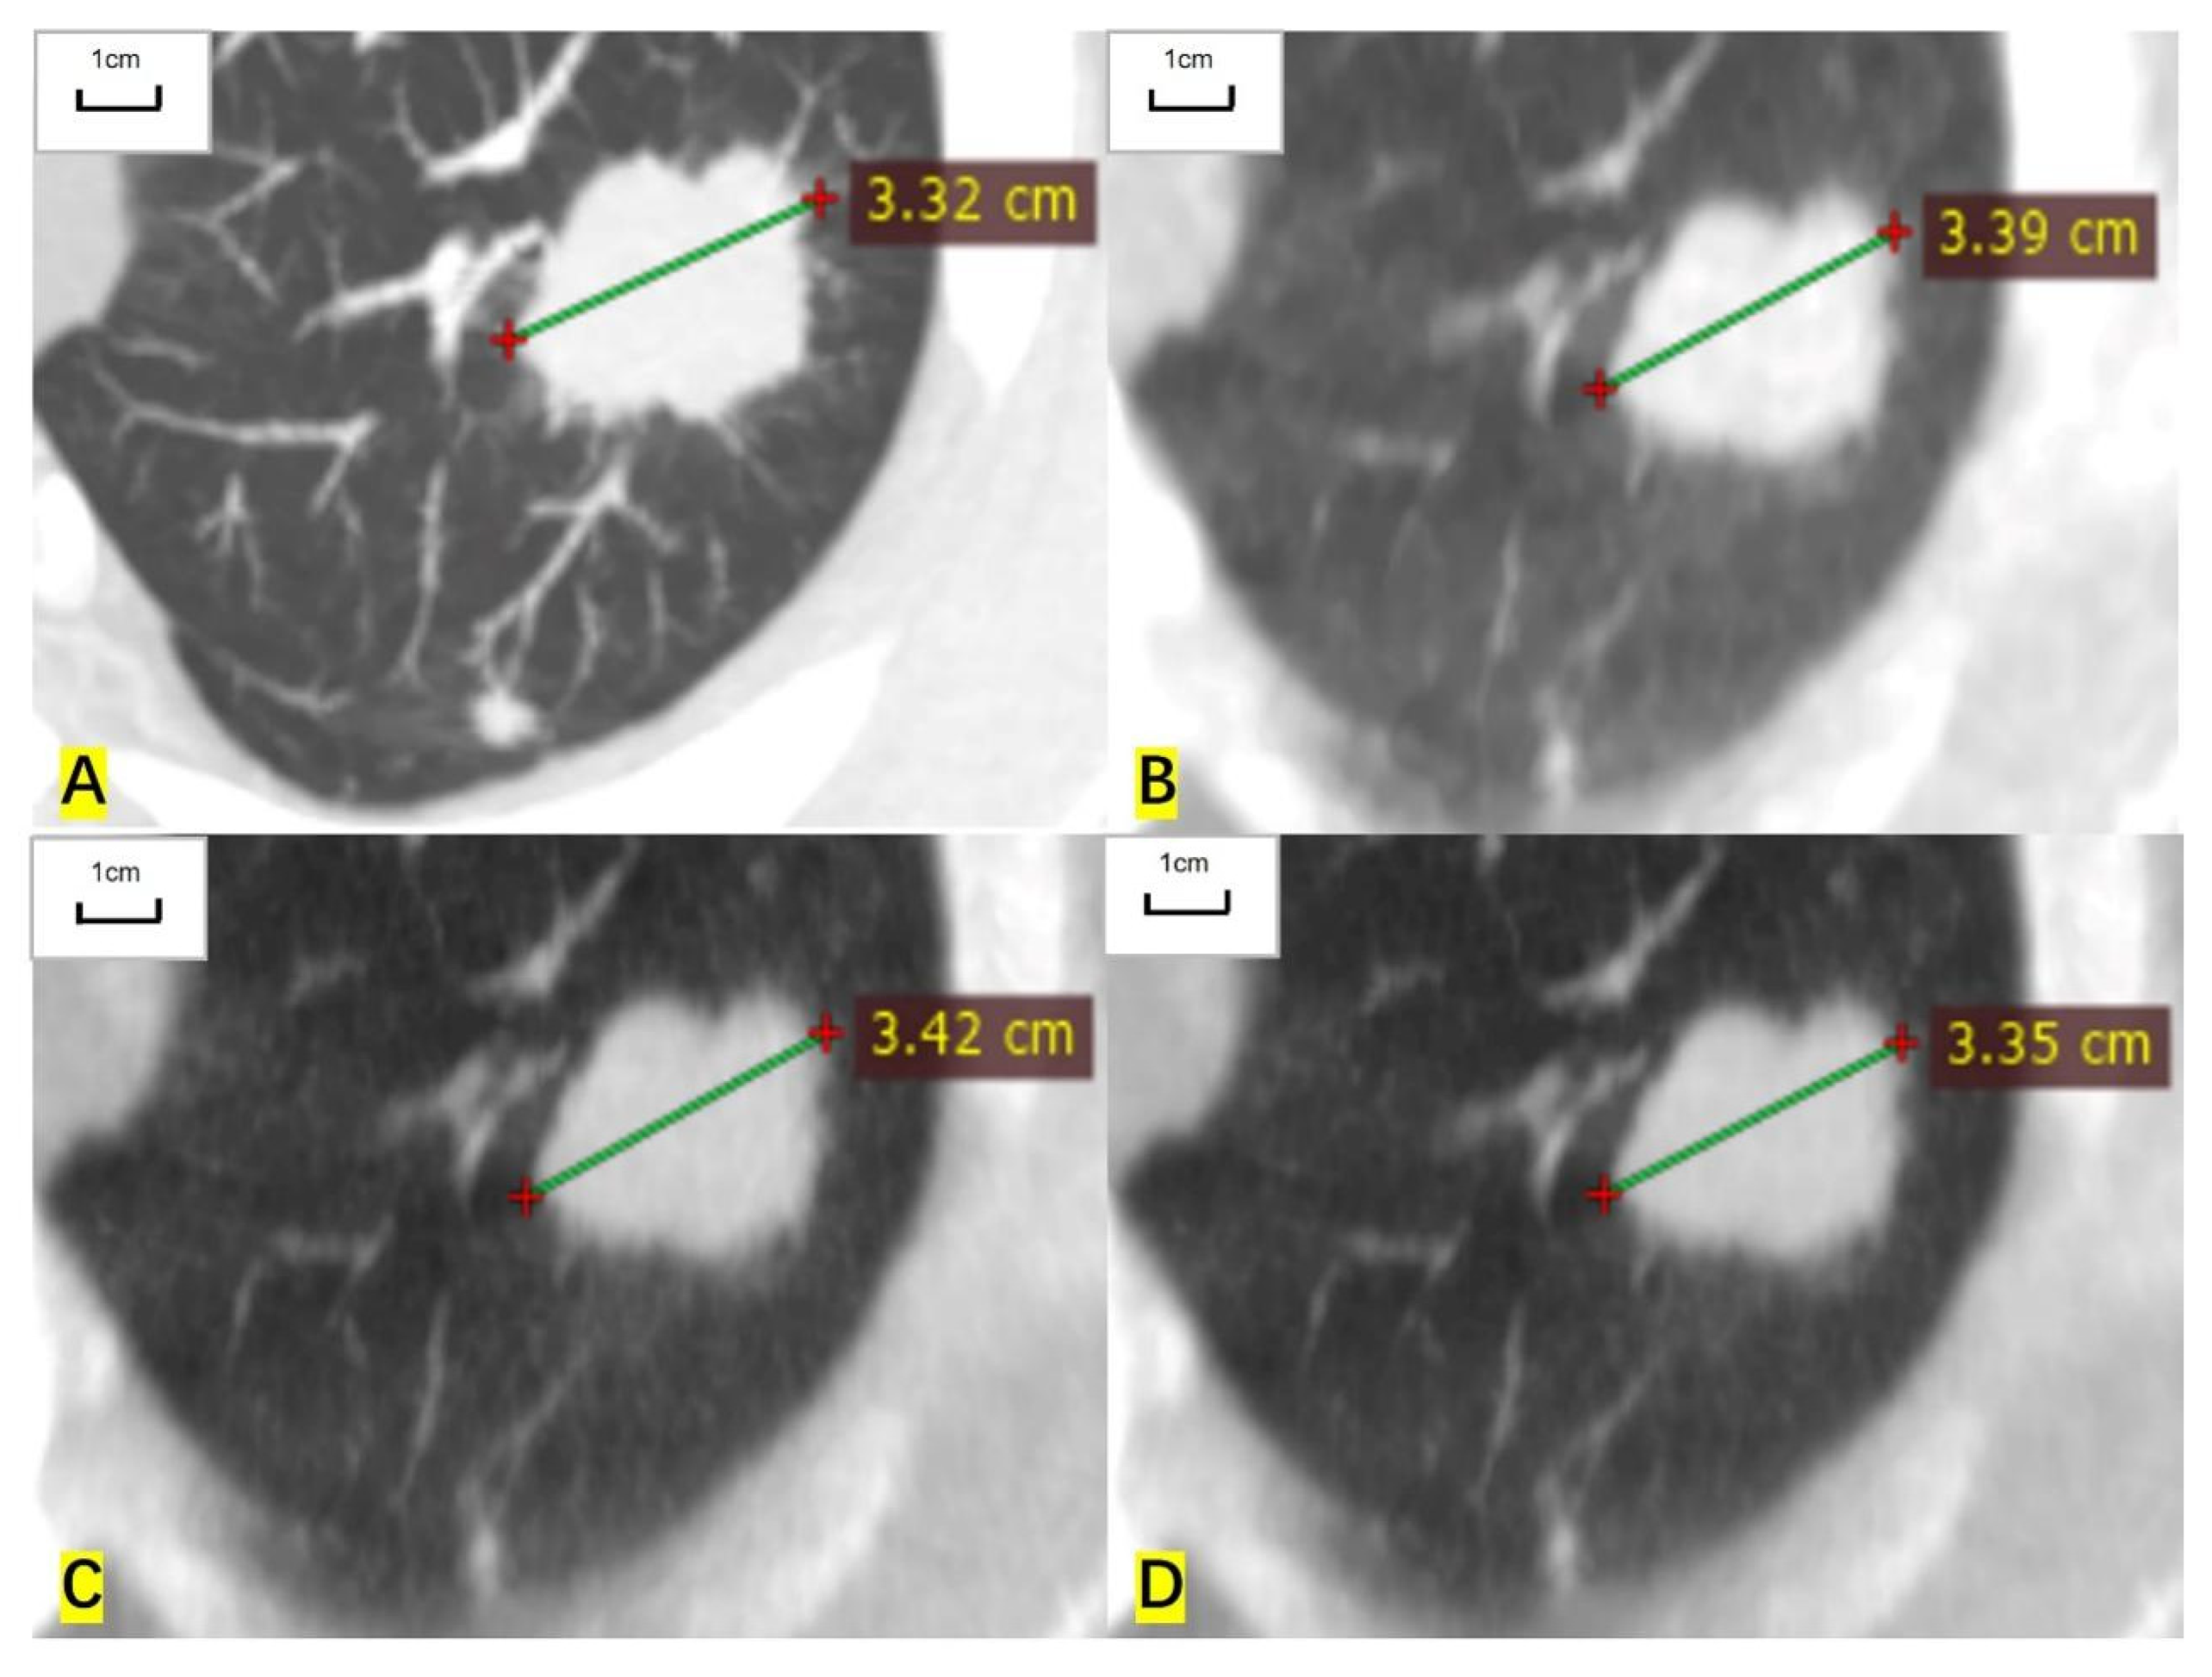

Figure 1.

A 57-year-old man had a measurable target lesion in the upper lobe of the left lung and the histological result was lung adenocarcinoma. (A) The long diameter measured on the contrast-enhanced CT image is 33.2 mm. (B) The measured long diameter on the ASIR-V-80% reconstructed image is 33.9 mm. (C) The measured long diameter on the DLIR-M image is 34.2 mm. (D) The measured long diameter on the DLIR-H images is 33.5 mm. The long diameter is overestimated by 2.1%, 3.0%, and 0.9%, respectively, compared with that of contrast-enhanced CT.

For RECIST-defined pulmonary target lesions, the correlation coefficient of measured diameter between ULDCT and contrast-enhanced CT was 0.999 (95% CI: 0.998 to 0.999), 0.998 (0.997 to 0.999), and 0.999 (0.999 to 1.000) for ASIR-V-80%, DLIR-M, and DLIR-H images, respectively. For mediastinal lymph nodes, the correlation coefficient was 0.997 (0.995 to 0.999), 0.997 (0.995 to 0.998), and 0.999 (0.998 to 1.000), respectively. For hilar lymph nodes, the correlation coefficient was 0.993 (0.979 to 0.997), 0.995 (0.984 to 0.998), and 0.997 (0.991 to 0.998), respectively. The measured diameters of target lesions in ULDCT were highly correlated with those in contrast-enhanced CT (Table 2, Figure 1 and Figure 2).